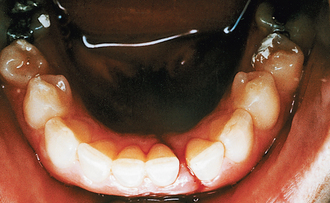

Examination of the mouth with a good light, paying attention to the junction of the hard and soft palate (Le Fort pattern fractures cause haematomas here), dental arches and the sulci, is important. The teeth should be charted, noting particularly broken teeth and retained roots, especially those that are very mobile and which may cause airway embarrassment. Gentle but purposeful pressure should be applied to all teeth to detect possible dentoalveolar fractures, a split palate and fractured teeth. Patients with fractures of the mandible between the mental foramen and the mandibular foramen often have reduced levels of sensation in the distribution of the inferior alveolar or lingual nerves and patients with zygomatic fractures often have areas of reduced sensation in the distribution of the infraorbital and anterior superior alveolar nerves. Any such areas of altered sensation should be recorded. Intraoral soft-tissue injuries are usually obvious and some extensive lacerations of the hard and soft palate may be present—for example, if a child has impacted a toy or other object into the mouth during a fall. Sublingual haematomas and tears at the gingival margin can be diagnostic of mandibular fractures (Fig. 13.4).

image

Fig. 13.4 Torn gingiva and haematoma of floor of mouth.